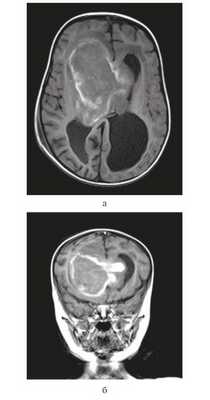

Девочка в возрасте 11 мес. Заболела остро, после перенесенной легкой черепно-мозговой травмы — упала с высоты собственного роста, после чего стала утрачивать приобретенные навыки: перестала стоять, сидеть, появилась вялость, адинамия, срыгивания. При МРТ головного мозга выявлена гигантская опухоль боковых и III желудочков, окклюзионная гидроцефалия (рис. 1).

![]()

Рисунок 1. Магнитно-резонансные томограммы грудного ребенка 11 мес с гигантской внутрижелудочковой опухолью. а — Т1 с контрастным усилением, аксиальный срез, б — Т1 с контрастным усилением, фронтальный срез.